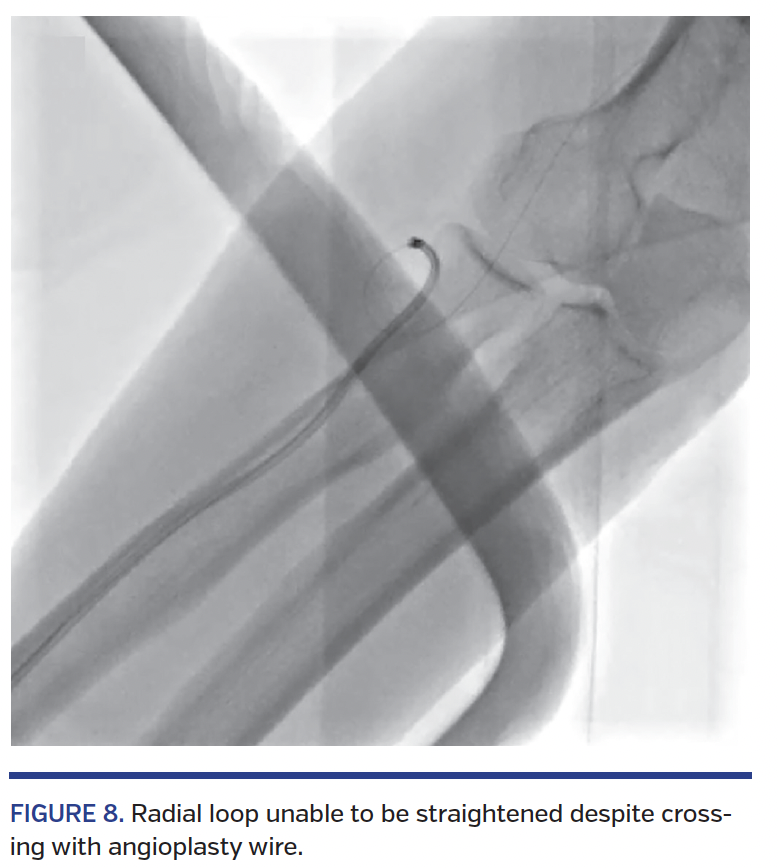

Subclavian tortuosity had a 73% success rate; these vessels were negotiated using hydrophilic wires and/or breathing maneuvers (deep inspiration) that aided in straightening of the loop. Despite these successes, operators must be aware that catheter manipulation during intubation of coronary arteries can be challenging and may result in knotting of the catheters and entrapment, which can be quite difficult to extract and may even require surgical intervention.29-33 If the tortuosity or loops do not straighten despite crossing, then the catheters are vulnerable to knotting during manipulation (Figure 8). Brachial tortuosity and spasms offered few problems, and most were negotiated with catheter manipulation, vasodilators, and hydrophilic wires.